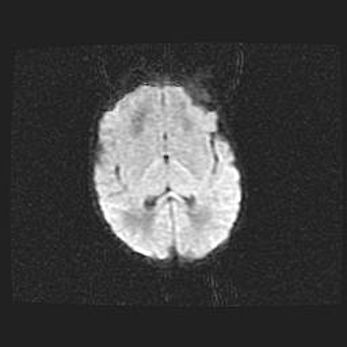

Церебральная ишемия II.

Возраст: 5 дней

Вес: 3400 г

Пол: женский

Окружность головы: 35 см

Срок гестации: 39 недель

Церебральная ишемия – это заболевание, характеризующееся недостаточностью (гипоксией) либо полным прекращением (аноксией) снабжения мозга кислородом по причине закупорки одного или нескольких сосудов. Это приводит к  что метаболическим расстройствам различной степени тяжести в тканях головного мозга, развитию коагуляционных некрозов и гибели нейронов.